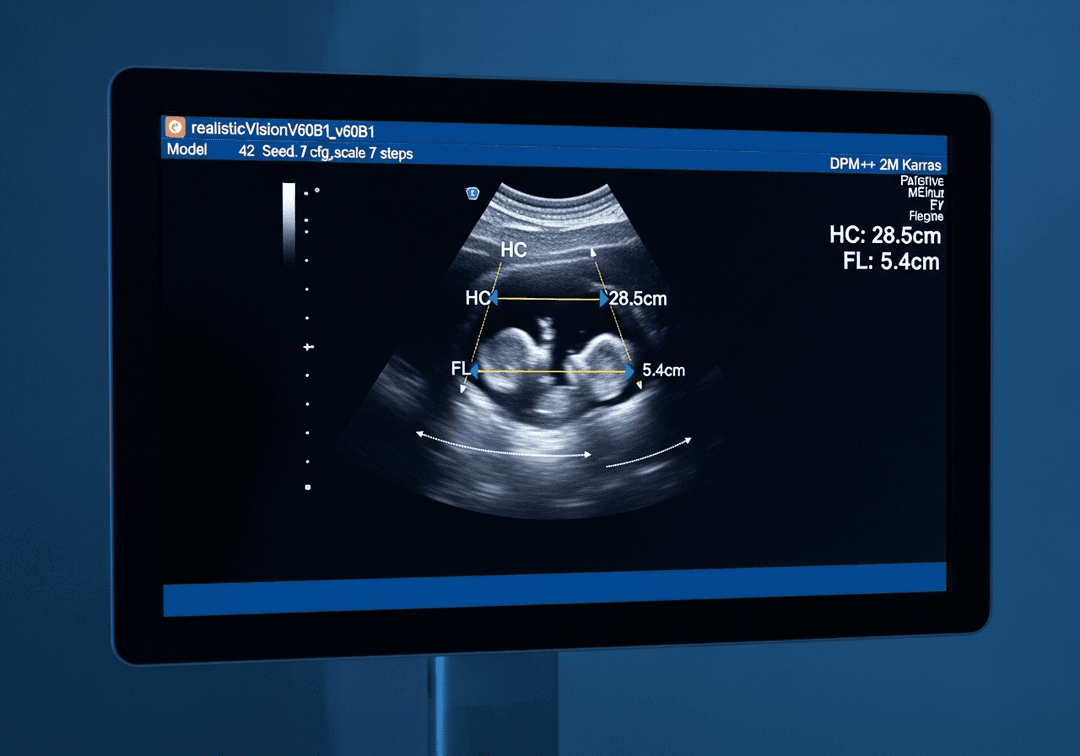

À partir de l'échographie du 2ème trimestre, quatre mesures biométriques sont systématiquement effectuées pour évaluer la croissance fœtale :

- BIP (Diamètre BiPariétal) : largeur de la tête entre les deux os pariétaux

- PC (Périmètre Crânien) : tour de tête du fœtus

- PA (Périmètre Abdominal) : tour du ventre, reflet de la nutrition

- LF (Longueur Fémorale) : longueur de l'os de la cuisse

Ces quatre mesures permettent d'estimer le poids fœtal (EPF), avec une marge d'erreur de 10 à 15%. Seul votre praticien peut interpréter ces mesures dans le contexte global de votre grossesse.

Au 2ème trimestre (22 SA), les valeurs moyennes sont approximativement : BIP 52 mm, PC 195 mm, PA 170 mm, LF 38 mm. Au 3ème trimestre (32 SA) : BIP 82 mm, PC 295 mm, PA 280 mm, LF 62 mm.